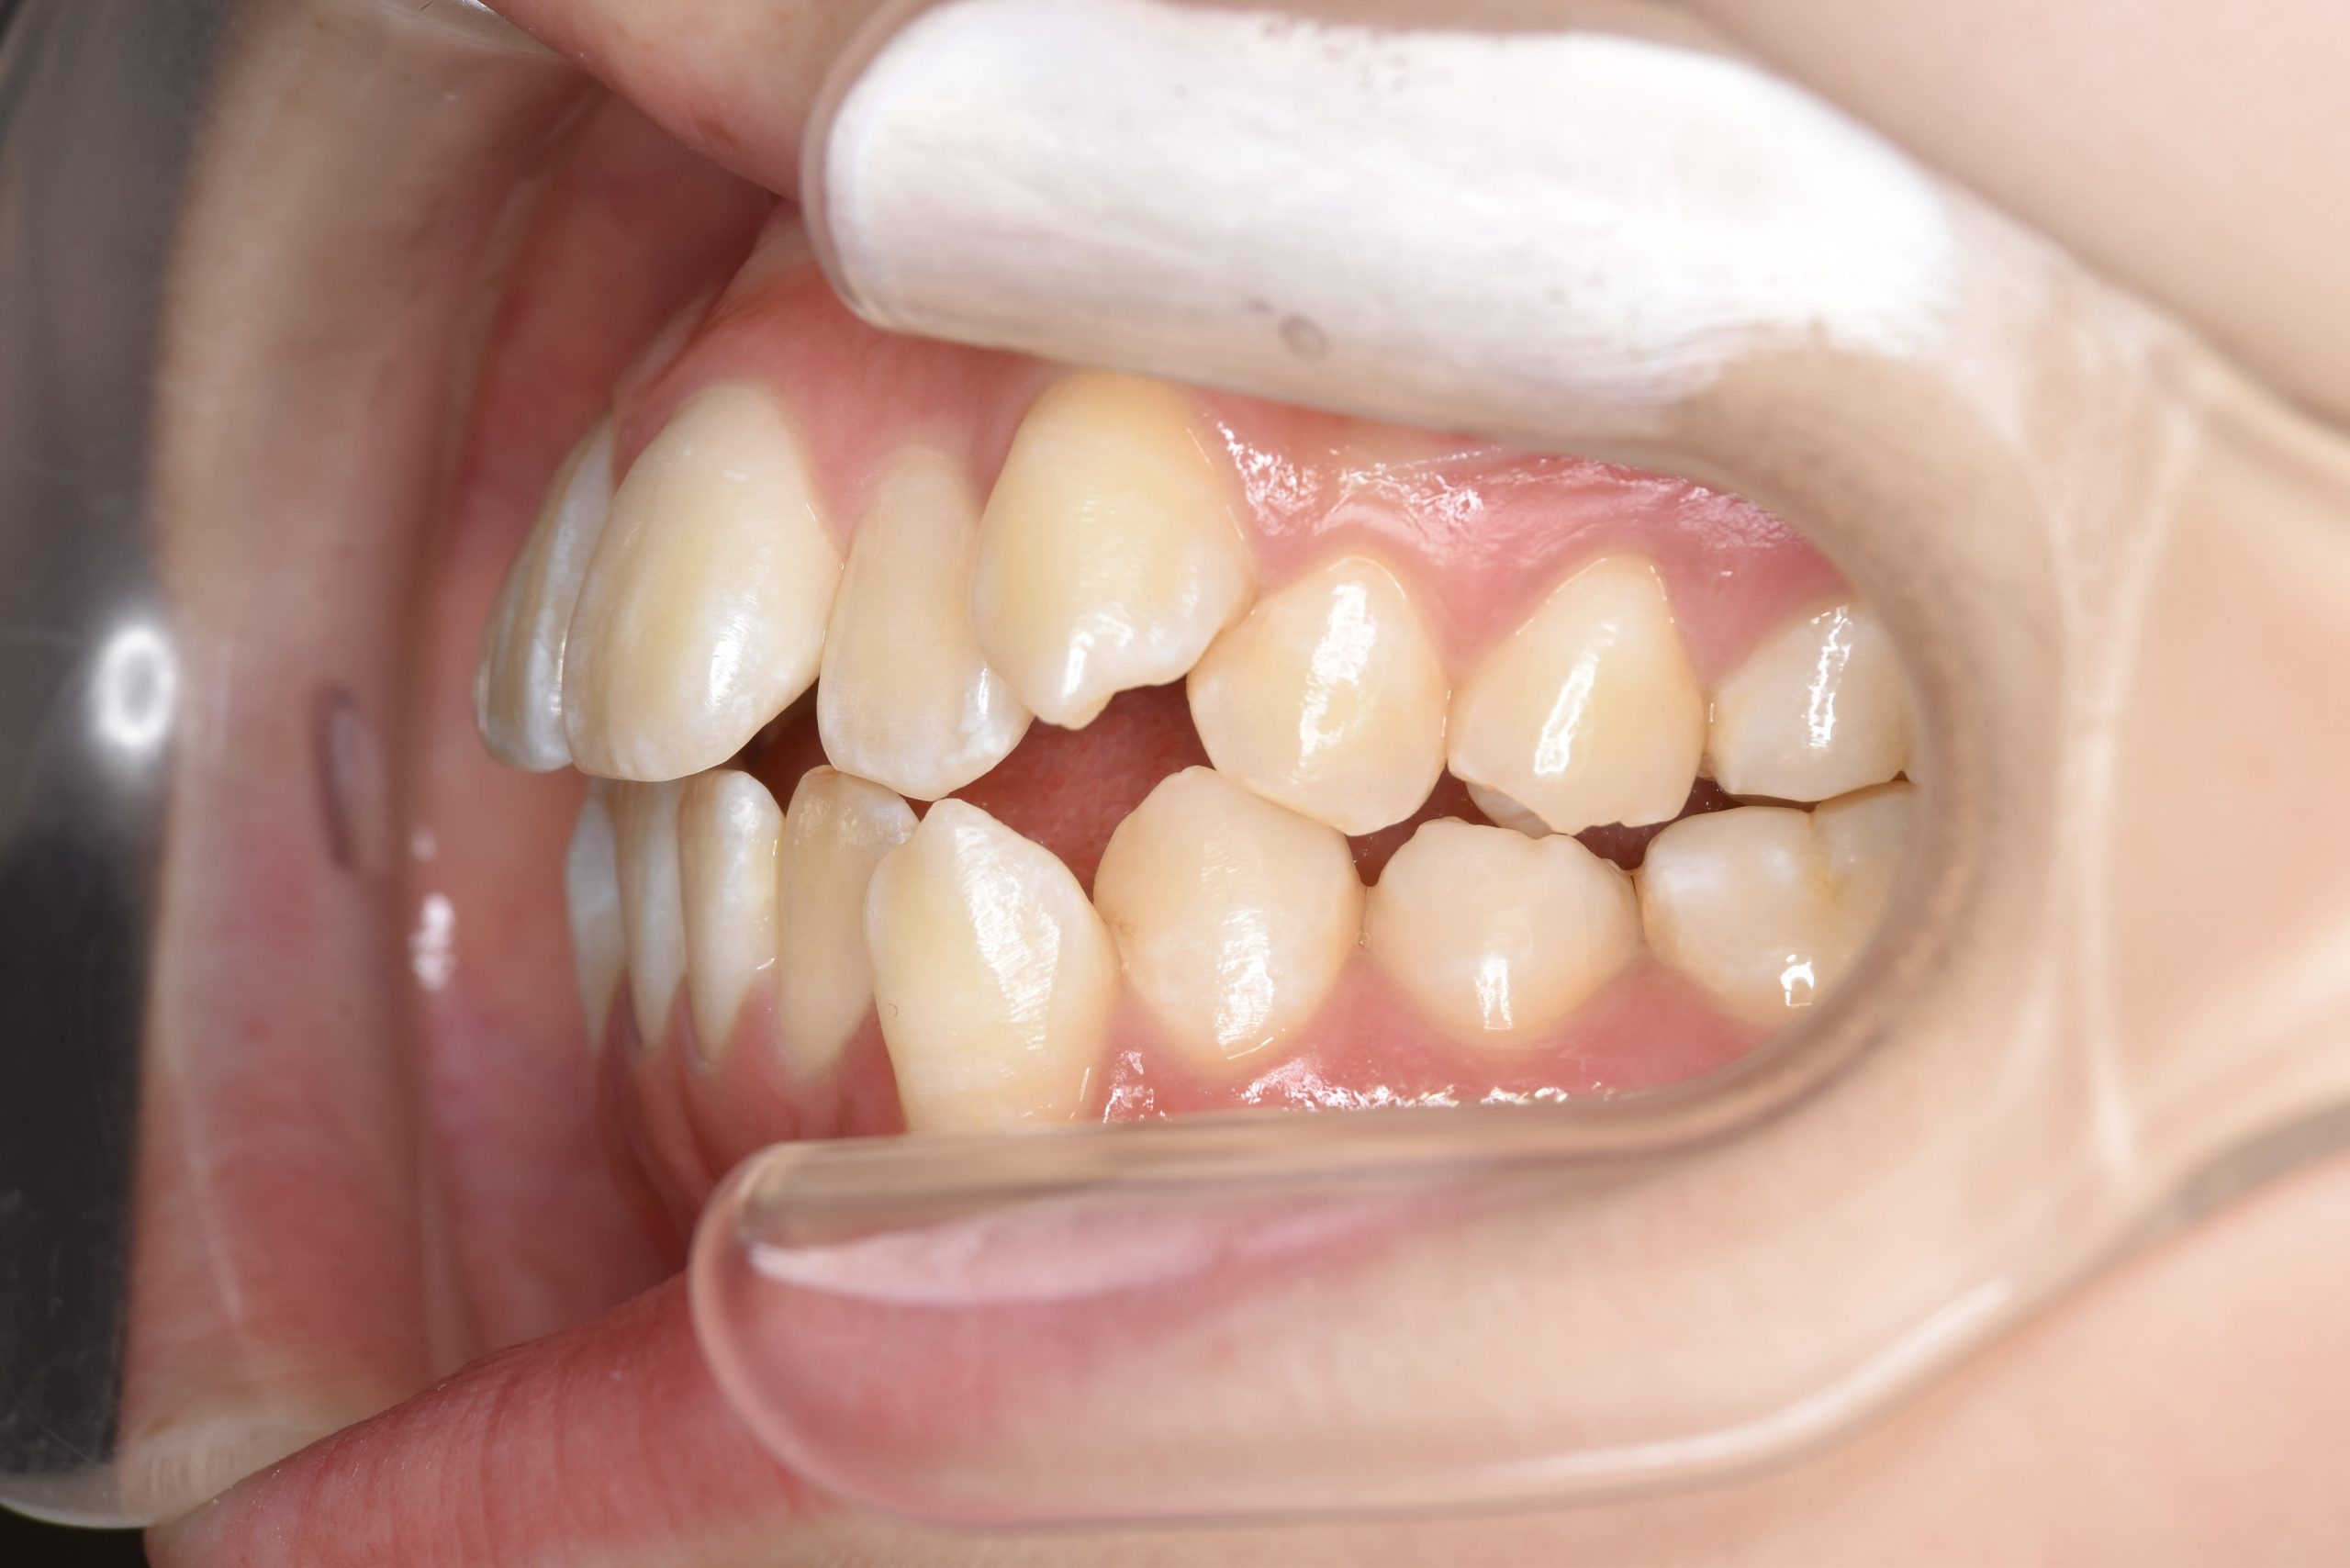

ビフォー

全顎ワイヤー矯正 症例_815

主訴 前歯の出っ歯|八重歯|下の歯のデコボコ|検診で噛み合わせが悪いと指摘されたこと

施術内容 成人矯正1期治療

治癒期間 1年4か月間

費用 954,800円(税込)